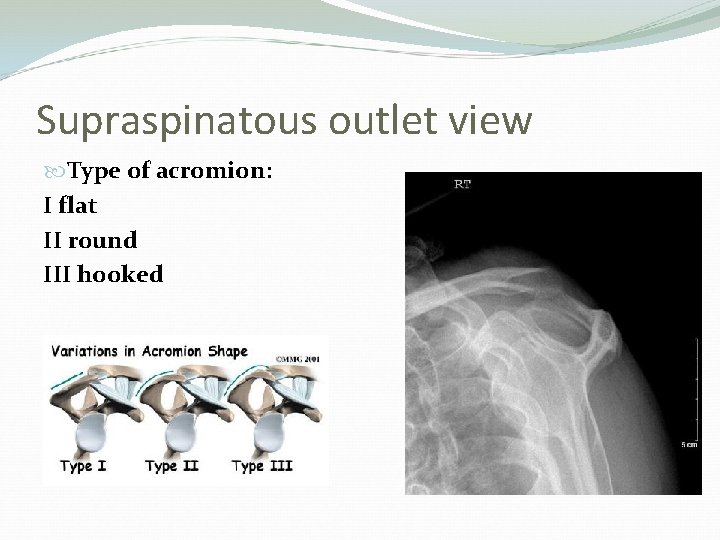

Bones Humerus. Scapula (acromin): Type I : flat Type II: curved Type III: hooked Clavicle

Supraspinatous outlet view Type of acromion: I flat II round III hooked